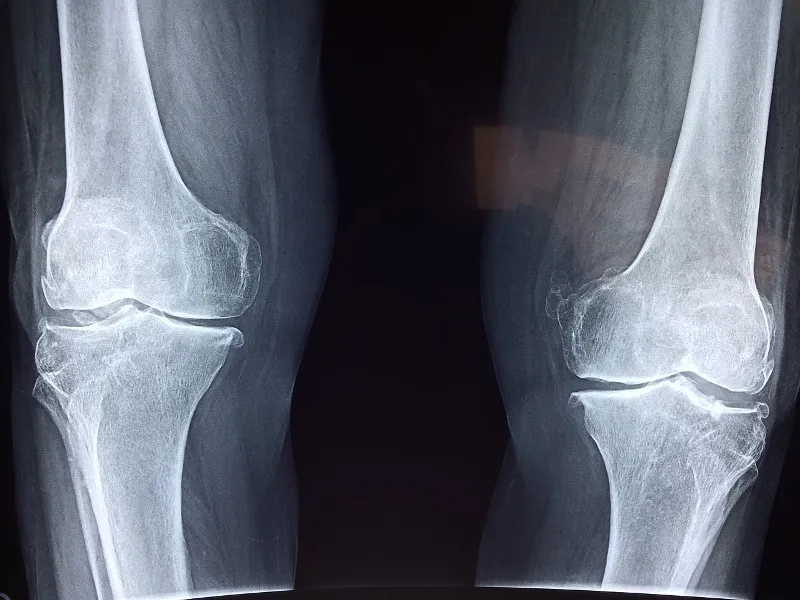

In deinem Kniegelenk hast du zwei Menisken. Diese Menisken bestehen aus Knorpel und haben die Form eines Halbmondes. So hat man den Aussenmeniskus und den Innenmeniskus (sehe Bild)

Die Funktion dieser Menisken ist Stossdämpfung und der Schutz von deinem Knorpel von Unterschenkel (Tibia) und Oberschenkel (Femur) die sich als Schutzhülle über deine Knochen legt.